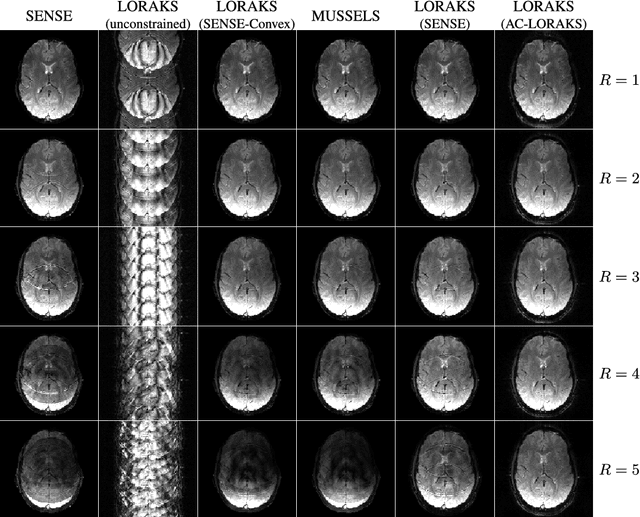

Abstract:Purpose: We propose and evaluate a new structured low-rank method for EPI ghost correction called Robust Autocalibrated LORAKS (RAC-LORAKS). The method can be used to suppress EPI ghosts arising from the differences between different readout gradient polarities and/or the differences between different shots. It does not require conventional EPI navigator signals, and is robust to imperfect autocalibration data. Methods: Autocalibrated LORAKS is a previous structured low-rank method for EPI ghost correction that uses GRAPPA-type autocalibration data to enable high-quality ghost correction. This method works well when the autocalibration data is pristine, but performance degrades substantially when the autocalibration information is imperfect. RAC-LORAKS generalizes Autocalibrated LORAKS in two ways. First, it does not completely trust the information from autocalibration data, and instead considers the autocalibration and EPI data simultaneously when estimating low-rank matrix structure. And second, it uses complementary information from the autocalibration data to improve EPI reconstruction in a multi-contrast joint reconstruction framework. RAC-LORAKS is evaluated using simulations and in vivo data, and compared to state-of-the-art methods. Results: RAC-LORAKS is demonstrated to have good ghost elimination performance compared to state-of-the-art methods in several complicated acquisition scenarios (including gradient-echo brain imaging, diffusion-encoded brain imaging, and cardiac imaging). Conclusion: RAC-LORAKS provides effective suppression of EPI ghosts and is robust to imperfect autocalibration data.

Abstract:We propose and evaluate a new MRI reconstruction method named LORAKI that trains an autocalibrated scan-specific recurrent neural network (RNN) to recover missing k-space data. Methods like GRAPPA, SPIRiT, and AC-LORAKS assume that k-space data has shift-invariant autoregressive structure, and that the scan-specific autoregression relationships needed to recover missing samples can be learned from fully-sampled autocalibration (ACS) data. Recently, the structure of the linear GRAPPA method has been translated into a nonlinear deep learning method named RAKI. RAKI uses ACS data to train an artificial neural network to interpolate missing k-space samples, and often outperforms GRAPPA. In this work, we apply a similar principle to translate the linear AC-LORAKS method (simultaneously incorporating support, phase, and parallel imaging constraints) into a nonlinear deep learning method named LORAKI. Since AC-LORAKS is iterative and convolutional, LORAKI takes the form of a convolutional RNN. This new architecture admits a wide range of sampling patterns, and even calibrationless patterns are possible if synthetic ACS data is generated. The performance of LORAKI was evaluated with retrospectively undersampled brain datasets, with comparisons against other related reconstruction methods. Results suggest that LORAKI can provide improved reconstruction compared to other scan-specific autocalibrated reconstruction methods like GRAPPA, RAKI, and AC-LORAKS. LORAKI offers a new deep-learning approach to MRI reconstruction based on RNNs in k-space, and enables improved image quality and enhanced sampling flexibility.

Abstract:Structured low-rank matrix models have previously been introduced to enable calibrationless MR image reconstruction from sub-Nyquist data, and such ideas have recently been extended to enable navigator-free echo-planar imaging (EPI) ghost correction. This paper presents novel theoretical analysis which shows that, because of uniform subsampling, the structured low-rank matrix optimization problems for EPI data will always have either undesirable or non-unique solutions in the absence of additional constraints. This theory leads us to recommend and investigate problem formulations for navigator-free EPI that incorporate side information from either image-domain or k-space domain parallel imaging methods. The importance of using nonconvex low-rank matrix regularization is also identified. We demonstrate using phantom and \emph{in vivo} data that the proposed methods are able to eliminate ghost artifacts for several navigator-free EPI acquisition schemes, obtaining better performance in comparison to state-of-the-art methods across a range of different scenarios. Results are shown for both single-channel acquisition and highly accelerated multi-channel acquisition.